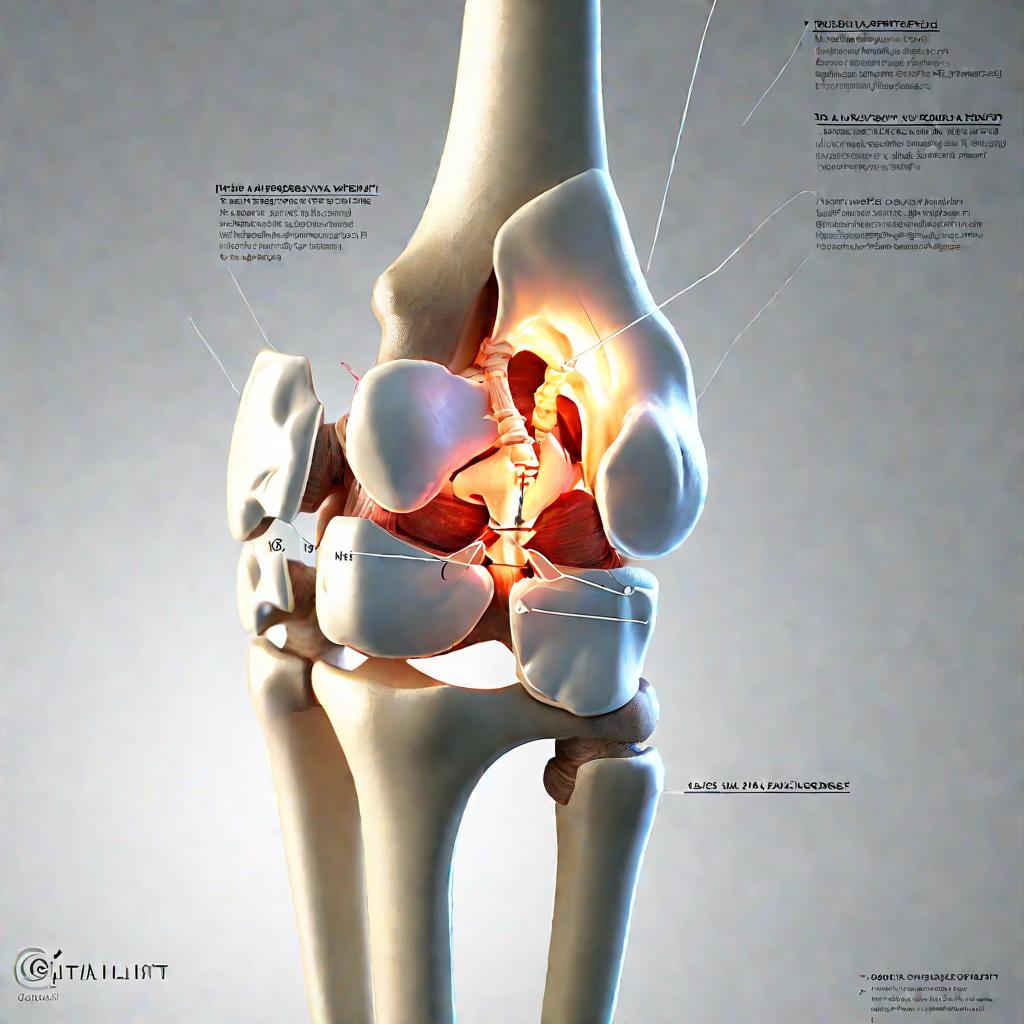

Диаграммы и схемы движения в суставах человека